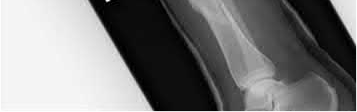

A 34-year-old male falls from a roof and sustains a right elbow dislocation that is closed reduced in the emergency room. An AP radiograph is shown in Figure A. This injury pattern is at highest risk for which of the following?

Anteromedial coronoid facet fracture and LCL injury following an elbow dislocation is commonly associated with varus posteromedial rotatory instability. Varus and posteromedial rotation force on the forearm results in rupture of the LCL from its humeral origin. As the LCL ruptures, the medial coronoid process is fractured as it impacts against and under the medial trochlea. Fracture involvement of the sublime tubercle, where the MCL attaches, can lead to more instability. Ulnar neuropathy can be seen following this injury pattern but AIN and PIN nerve palsy do not commonly characterize this injury pattern.

The review article by O'Driscoll highlights key points in diagnosis and management of capitellum, distal humerus, coronoid, and terrible triad injuries.

The article by Doornberg and Ring is a Level 4 study of 18 patients that sustained varus posteromedial rotational injuries resulting in anteromedial facet coronoid fractures. They found that lack of fixation at injury or malunion of the anteromedial facet were significant predictors of suboptimal functional outcome and development of arthrosis.

The anteromedial facet is highlighted in yellow as displayed in Illustration A. Illustration B depicts the lateral collateral ligament injury also evident during

varus stress fluroscopic examination, due to tension failure of the LCL off its humeral origin during the various mechanism.